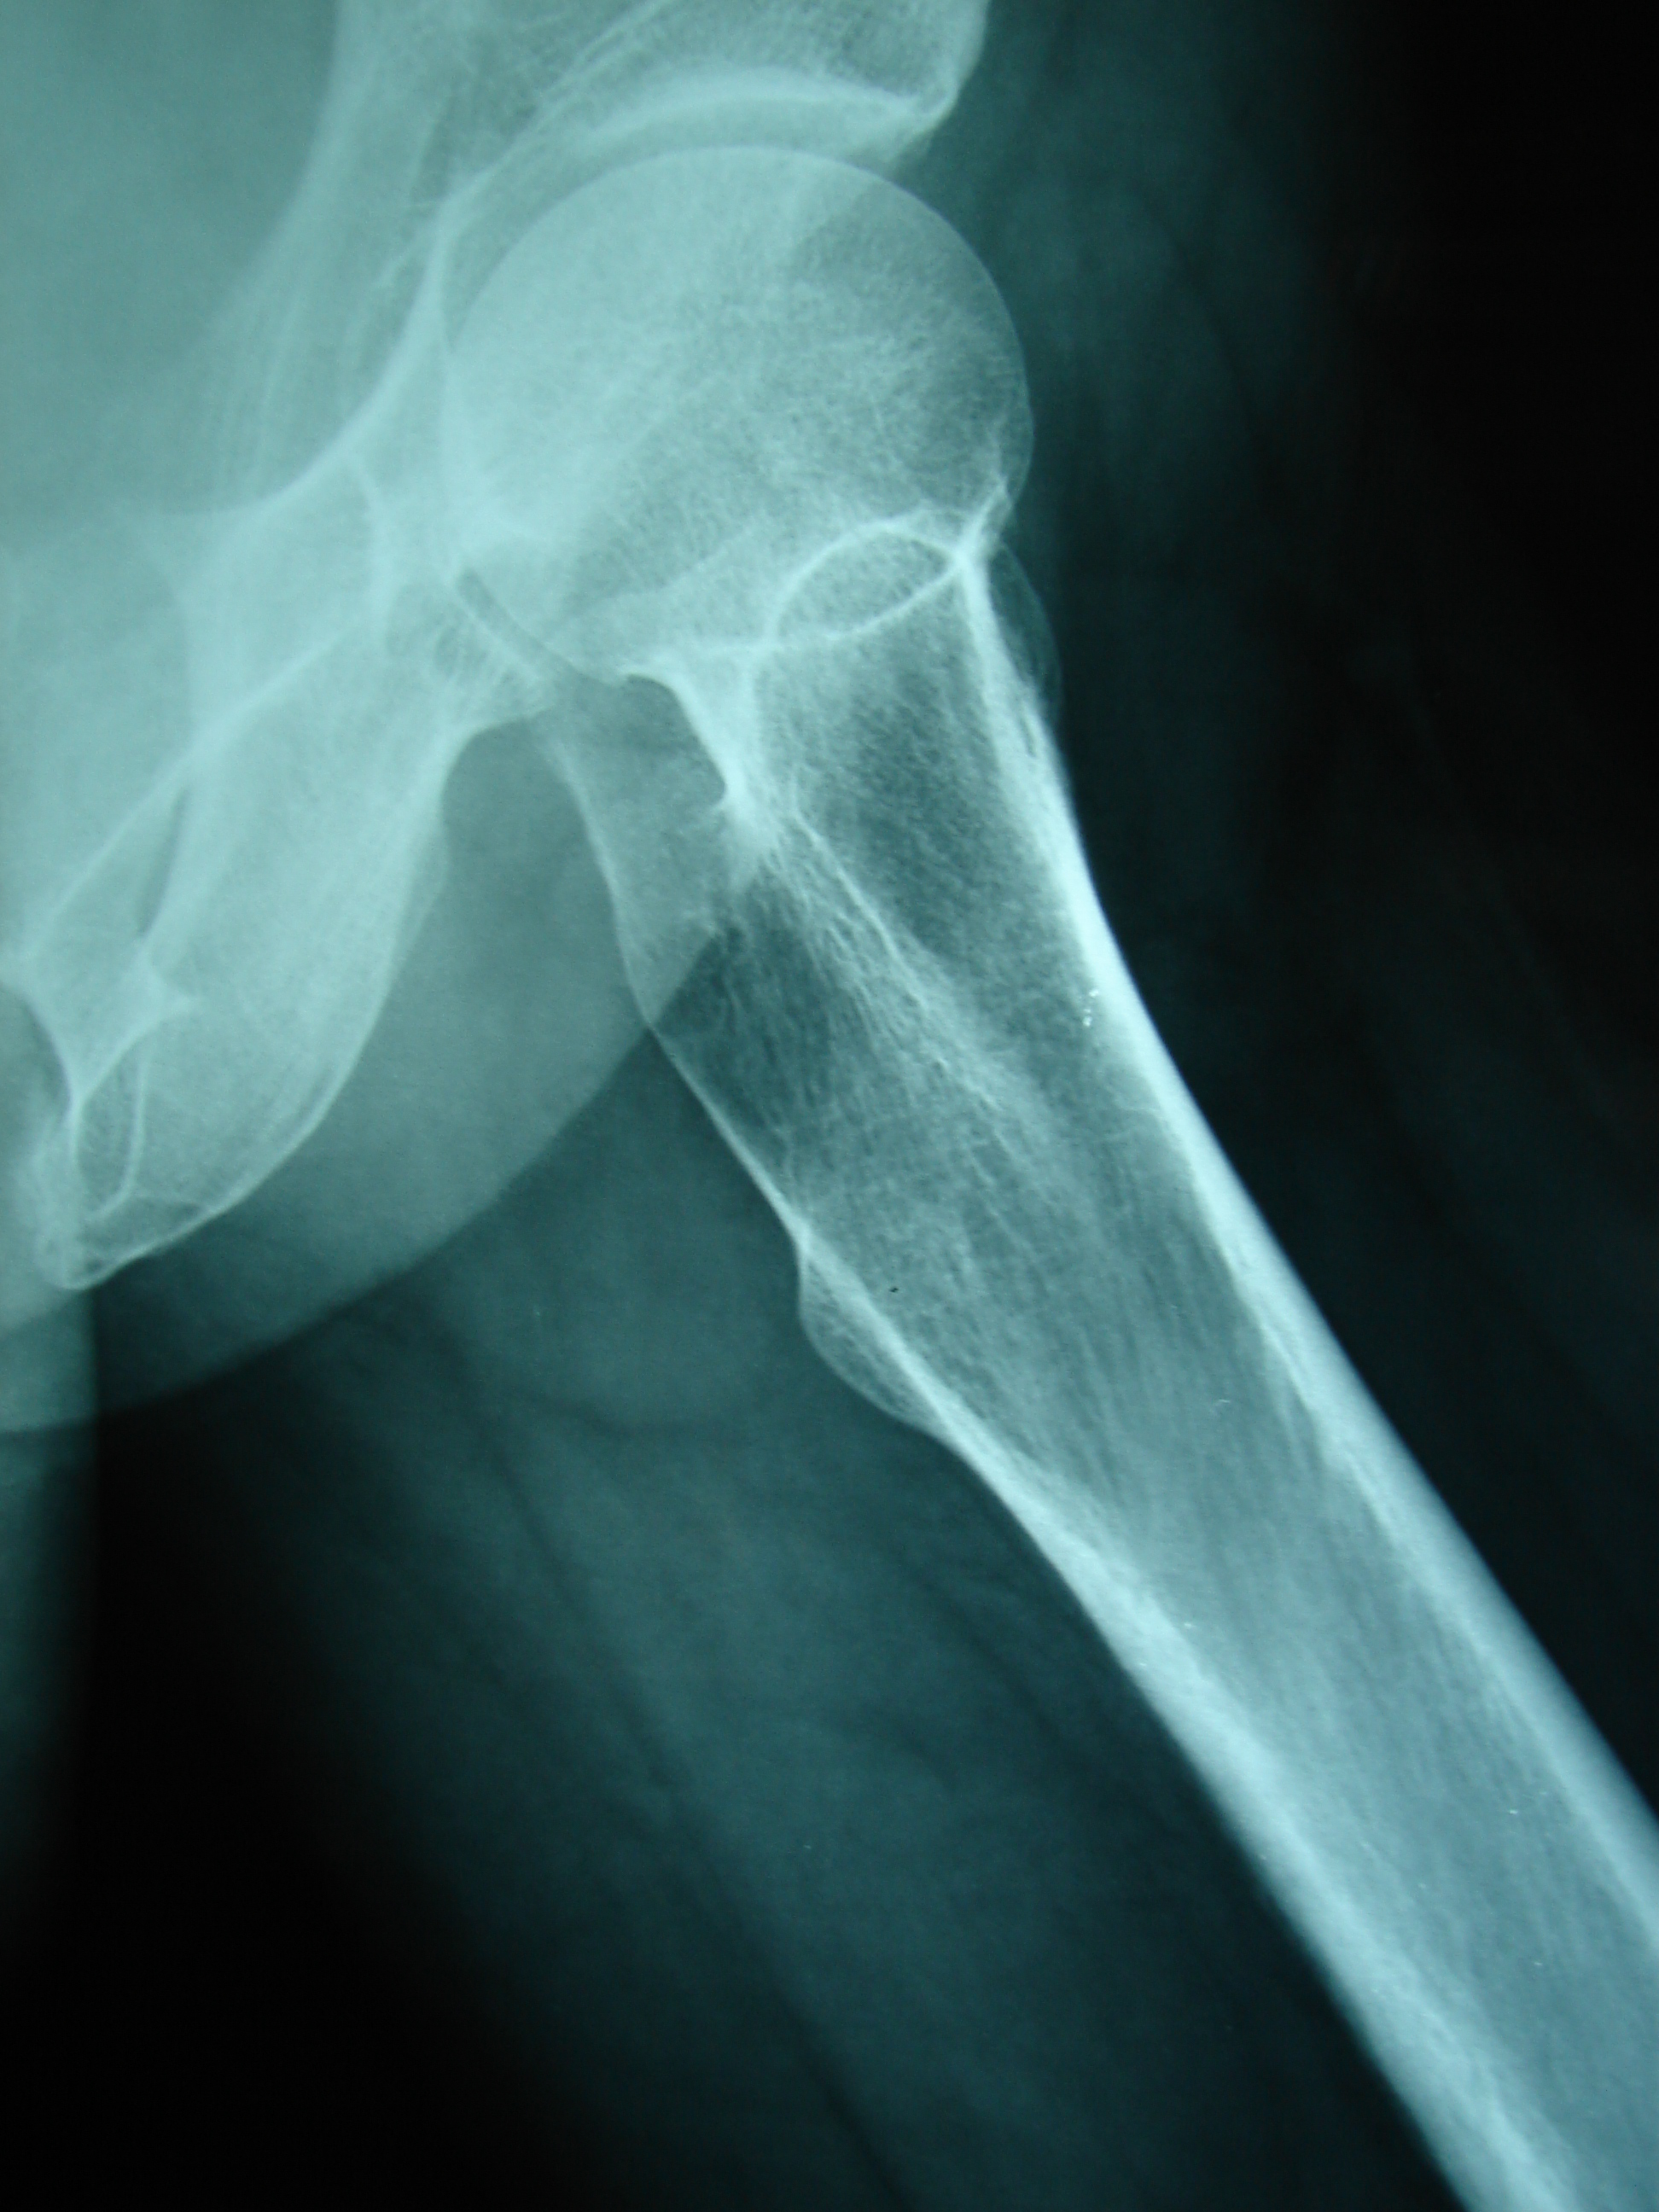

Μετά απο ένα έτος η Ελ. Λα. άρχισε να αιτιάται δια άλγος εντοπιζόμενο στην περιοχή του αριστερού ισχίου. Ο γενόμενος ραδιο-ισοτοπικός έλεγχος έδειξε αυξημένη συγκέντωση στη περιοχή του άνω τριτημορίου του αριστερού μηριαίου οστού. Για να αποτραπεί η πρόκληση παθολογικού κατάγματος του οστού εγένετο προφυλακτική ήλωση του μηριαίου οστού.

Μετά την σταθεροποιήση του πάσχοντος μηριαίου οστού η πάσχουσα απαλλάχθηκε απο τον πόνο και είχε την δυνατότητα να περπατά άνετα μεγάλες αποστάσεις.